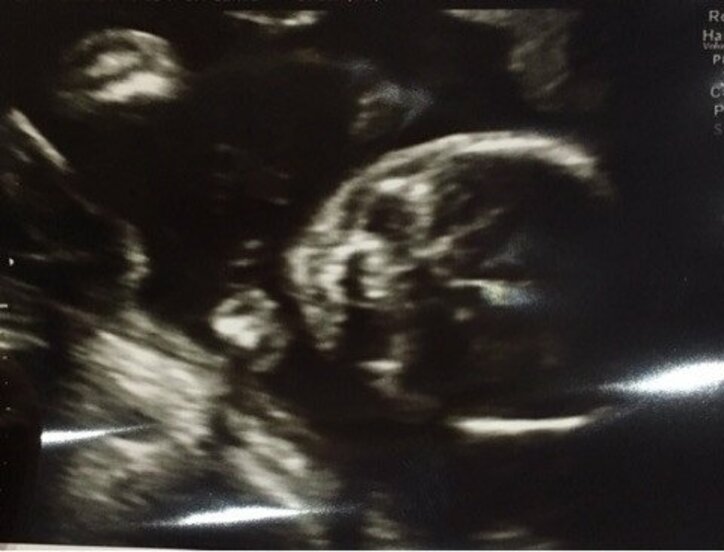

ぺこは「お仕事前にりゅうちぇると検診へ!」と報告。おなかの子どもの様子について、「とってもとっても元気に動いてくれてて、お顔も見えたよ わかるかな?」とエコー写真を公開した。「最近は胎動を感じるようになって、たくさん動いてくれててぽこぽこ蹴られてます笑」とおなかの子どもは元気いっぱいの様子。「胎動を感じるたびにかわいさが増して、にやにやが止まらない(たまにすんごい勢いのときはふつうに声出してわろてまう)」と幸せいっぱいにつづっている。